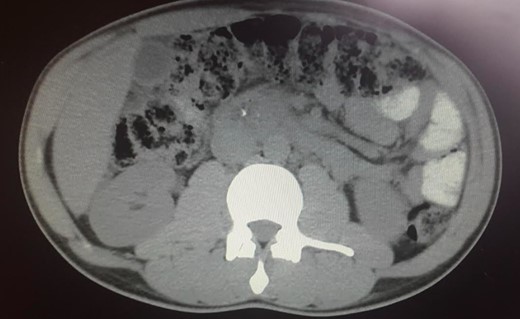

The abdominal exam revealed a soft, non-distended, non-tender abdomen, without any palpable masses, organomegalies or lymphadenopaties. Blood chemistry showed a cholestatic pattern: bilirubin 6.61 mg/dl, alkaline phosphatase 434 U/l, gamma-glutamyl transpeptidase 374 U/l, alanine transaminase 542 U/l and aspartate transaminase 228 U/l. Lipase, amylase and complete blood count showed regular values. Abdominal ultrasound revealed dilatation of the intra and extrahepatic bile ducts and the pancreas was enlarged and hypoechoic, compatible with inflammation. CT scan was performed to discard a neoplastic obstruction and confirmed an intrahepatic biliary ductal dilatation (Fig. 1) and a dilatation of the distal bile duct with no luminal lesions (Fig. 2).

Pancreatic CT scan. General dilatation of the intrahepatic biliary tree and terminal common bile duct.

Pancreatic CT scan. Dilatation of the distal bile duct, with no evidence of luminal lesions nor a pancreatic mass constricting the bile duct (endoluminal prosthesis).

Specific features in CT imaging for AIP suspicion are focal or diffuse pancreatic enlargement with loss of the lobular shape (sausage-shaped pancreas), a low-density rim surrounding the pancreas and delayed homogenous enhancement during venous phase [8], which were not present. The patient presented an intrahepatic and distal bile duct dilatation but no pancreatic masses or abnormal enlargements and no delayed homogeneous enhancement. If non-classic CT abdominal features, ERCP can be very helpful in identifying the presence of a narrow stricture (>one-third of the MPD) or multiple non-contiguous strictures and absence of upstream dilatation from the stricture [9]. ERCP showed a pseudonodular mass in the head of the pancreas but the pancreatic duct presented no strictures or irregular stenosis. Only the intrapancreatic portion of the common bile duct presented an irregular 2 cm length stenosis and an upstream dilatation, pointing to cholangiocarcinoma.